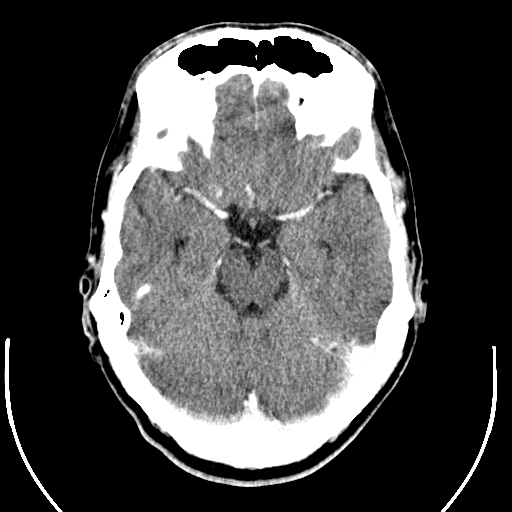

오늘은 임상에서 가장 자주 하게 되는 뇌 CT 검사 CT-Brain에 대해 글을 쓰려합니다.

뇌출혈, 뇌경색 등 뇌혈관질환과 뇌종양 션트(Shunt)위치 확인, 두개골의 기형 그리고 외상(trauma) 타박상(Contusion), 넘어짐(Fall down) 등 갑작스러운 사고 등으로 인한 뇌손상 등을 확인합니다.

안와를 포함하여 뇌전체가 포함되도록 하여 두개기저(Skull base)에서 마루점(Vertex)까지 스캔합니다

이때 1cut씩 검사하는 축 방향스캔(Sequence mode 또는 axial mode)이나 용적 자료(Volume

data)를 얻을 수 있는 나선형 스캔(Spiral scan 또는 helical scan)으로 한다.